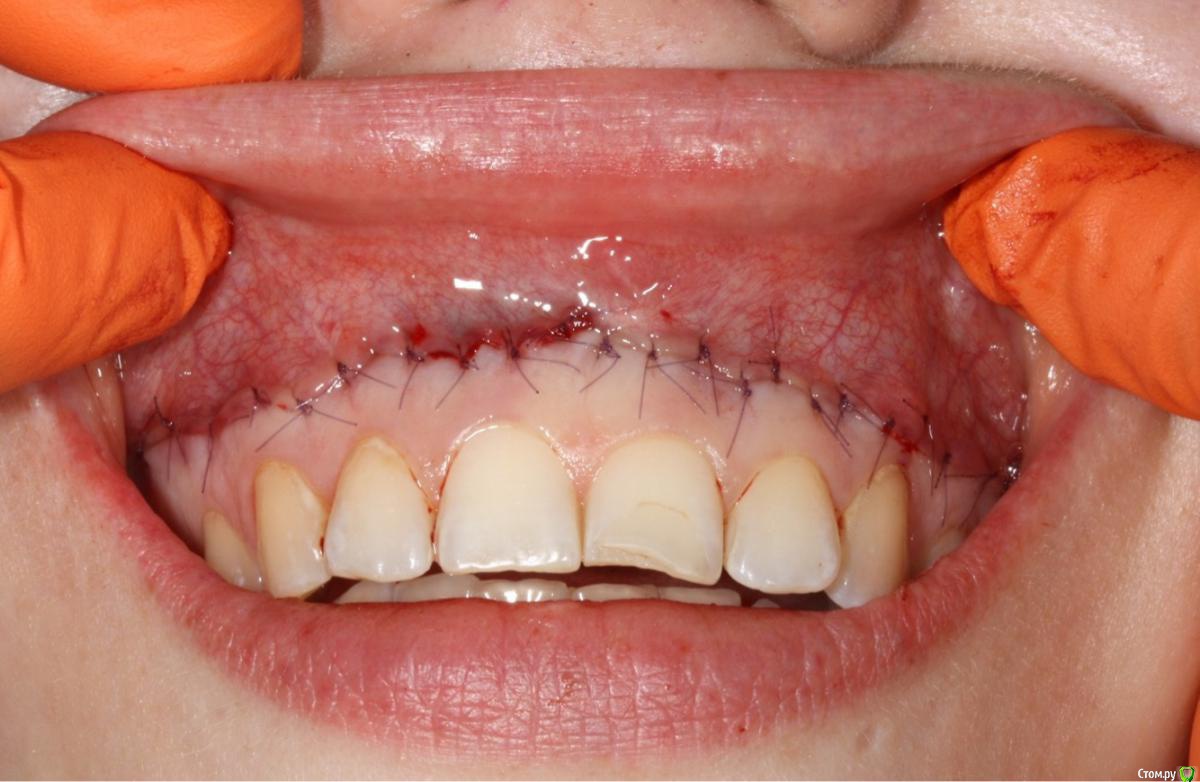

EdGein Опубликовано 12 февраля, 2019 Поделиться Опубликовано 12 февраля, 2019 Реверсивная вестибулопластика.Иссекается полоска эпителия выше слизисто-десневого соединения шириной примерно10-12 мм от шестерки до шестерки.Края раны ушиваются.Таким образом происходит репозиция нижней губы.Так же часто сочетается с удлинением клинических коронок зубов. 4 Ссылка на комментарий

EdGein Опубликовано 12 февраля, 2019 Поделиться Опубликовано 12 февраля, 2019 10-12 мм это в среднем.А так нужно замерять от зенита до края губы.Полоска иссекается до мышц. Травматичность минимальна, может быть небольшой отек, но не всегда.Уздечка и тяжы иссекаются, хотя есть методики в обход уздечки. 1 Ссылка на комментарий